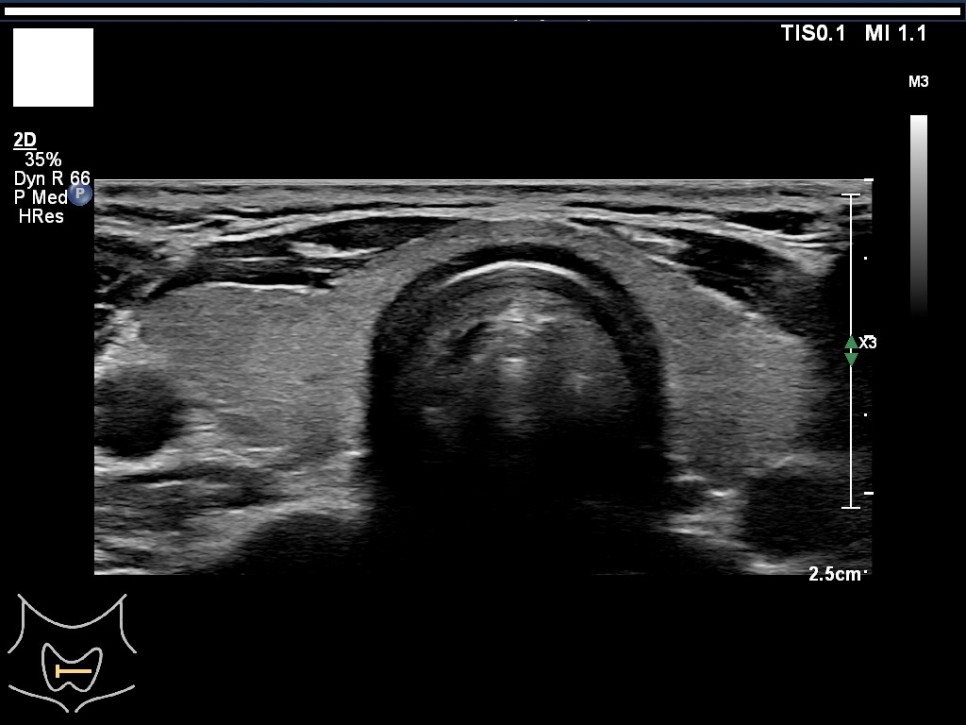

갑상선, 부갑상선 초음파 검사 급여 기준 1. 표준 영상의 범위 모든 영상에는 경부의 해부학적 위치(모식도나 문자)를 표기하여야 한다.

A) 병변이 없는 경우: 우엽 중부 가로 스캔, 우엽 중앙부 세로 스캔, 협부 가로 스캔, 좌엽 중부 가로 스캔, 좌엽 중앙부 세로 스캔, 우경부 림프절, 좌경부 림프절 나) 병변이 있는 경우: 병변이 없는 경우의 표준 영상과 함께 병변 부위에서 2개의 수직 관계 단면 영상(횡단/종단) 및 병변의 크기가 측정된 경우: 병변이 없는 경우의 표준 영상